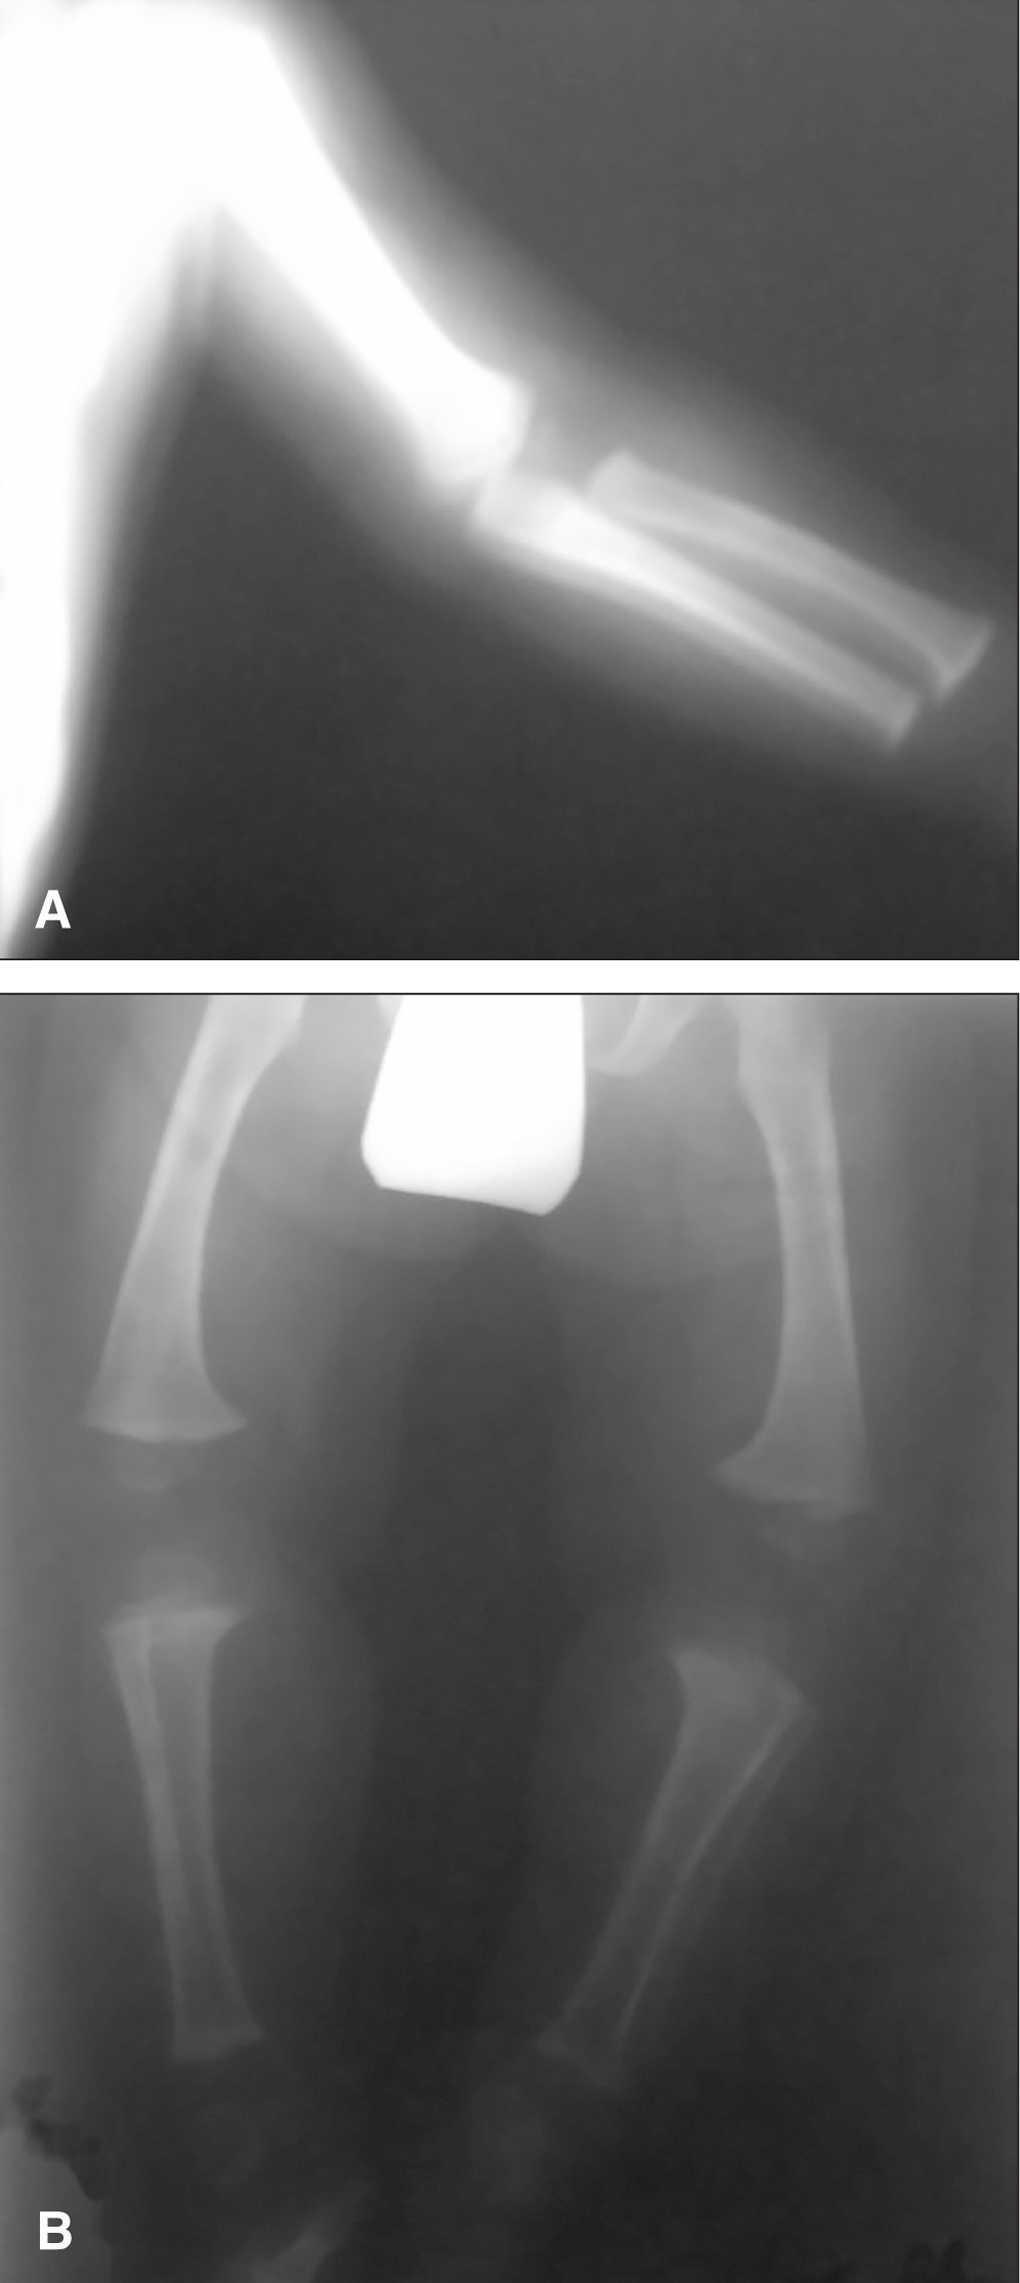

2. Mapas óseos (edad 16 meses): acortamiento de miembros, disminución de longitud de fémures y húmeros con metáfisis anchas y toscas. Disminución de la distancia interpedicular de las últimas vértebras lumbares. Hipoplasia del tercio inferior de ambos ilíacos con horizontalización de los acetábulos. Ensanchamiento de arcos costales (fig. 1).

Figura 1. Acortamiento de miembro superiorA)e inferioresB), con disminución de longitud de fémures y húmero, con metáfisis anchas y toscas.